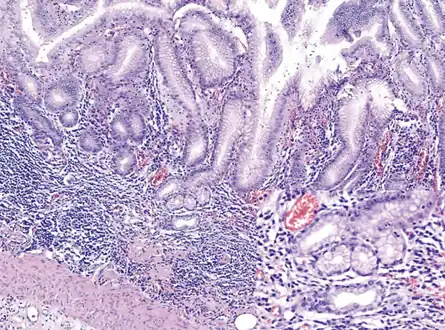

Atrophic gastritis

Atrophic gastritis under low power. H&E stain.

Histopathology of antral mucosa with atrophy. H&E 10x. Antral gastric mucosa with accentuated atrophy because replacement by extensive intestinal metaplasia.